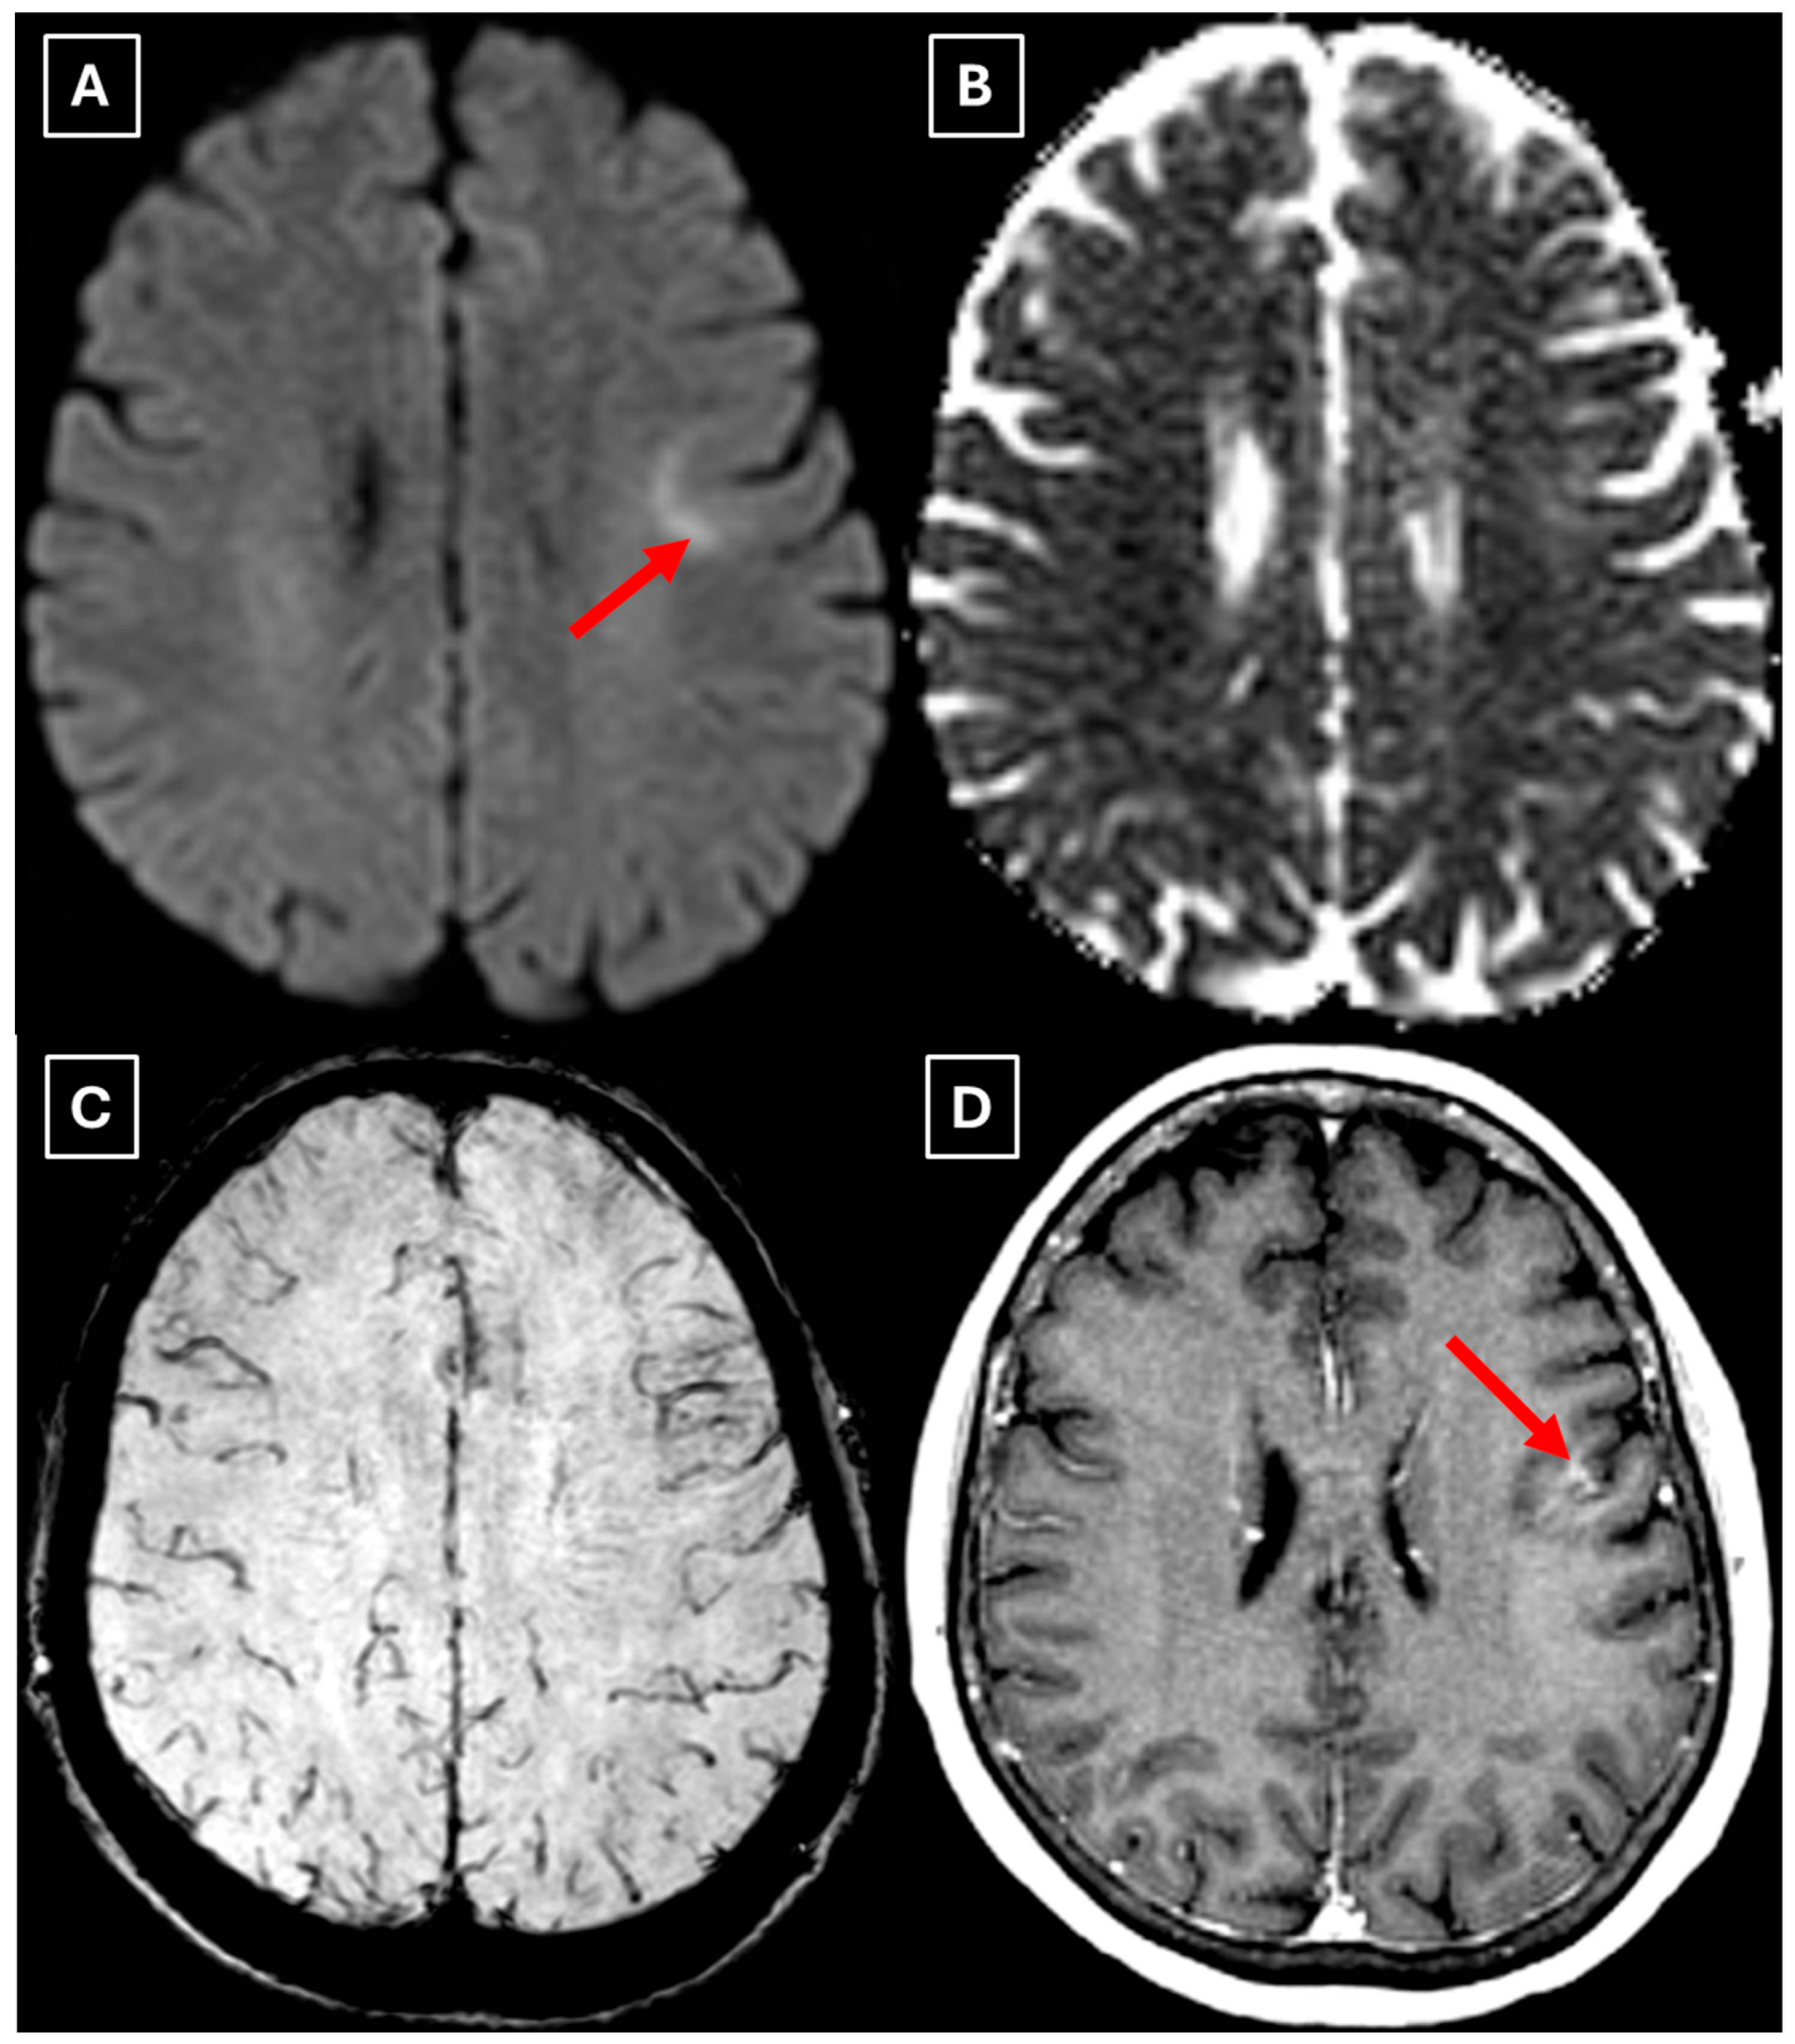

Figure 3. MRI scan of the brain. (A): Axial trace image of diffusion-weighted imaging (DWI) shows slight diffusion restriction in the lesion wall when correlated with (B): dark signal on apparent diffusion coefficient (ADC) maps in the wall of the lesion, with no central diffusion reduction observed. (C): In the corresponding axial slice of the susceptibility-weighted imaging (SWI) sequence, there is no evidence of blood products within the lesion. (D): On the axial postcontrast T1-weighted imaging, there is no contrast enhancement in the lesion, although a central vein-like structure is observed. Red arrow—diffusion restriction, yellow arrow—perifocal vasogenic edema, green arrow—central vein sign.

Figure 5. Two-week follow-up MRI axial scan of the brain. (A): Axial trace from diffusion-weighted imaging shows a higher signal along the peripheral parts of the lesion with the absence of cytotoxic edema when correlated with (B): the ADC map. (C): Central vein sign is positive on the susceptibility-weighted imaging sequence and (D): axial postcontrast T1-weighted sequence. These findings were not typical for low-grade astrocytomas. Red arrow—diffusion restriction, yellow arrow—perifocal vasogenic edema, green arrow—central vein sign.

Finally, we provide a high-resolution MRI follow-up of two months’ duration showing near-complete regression of the lesion after corticosteroid therapy. The lesion decreased from 37.34 mm × 34.85 mm (AP × LL) to 24.87 mm × 29.71 mm following two weeks of corticosteroid therapy and after almost two months from the first MRI scan to minimal patchy contrast enhancement (Figure 7D). This marked decrease in the size of the lesion gives strong evidence that a demyelinating rather than neoplastic process is present.

There are no pathognomonic features for tumefactive demyelinating lesions, but there are still some MRI findings that support the diagnosis. TDLs appear larger than 2 cm and are most often located in the frontal or parietal regions. The supratentorial white matter, especially in subcortical and periventricular locations, is commonly affected. On T1-weighted images they usually demonstrate hypointensity and hyperintensity on T2-weighted images, consistent with demyelination. These lesions have a varying degree of perifocal edema and mass effect, but both are usually mild relative to the lesion size in comparison to neoplasms or abscesses. The most characteristic enhancement pattern is the open-ring (incomplete rim) enhancement, which is significantly more common in TDLs than closed-ring enhancement. The open ring typically faces the cortex or gray matter and is considered a strong supportive feature for TDL diagnosis [3,11,18]. Contrast enhancement is not a universal feature, as Lucchinetti et al. (2008) [1] reported that approximately 5% of TDLs on postcontrast T1-weighted MRI did not show enhancement in their study. This finding was also observed in this case (Figure 3D), as well as in the case presented by Zafar et al. (2022) [19]. Therefore, the absence of enhancement does not necessarily exclude a demyelinating pathology.

Another MRI feature strongly associated with TDLs is a central vein sign (CVS), which was also observed in this case (Figure 3, Figure 5, and Figure 7), currently being considered for inclusion in MS diagnostic criteria. On SWI or T2-weighted sequences, CVS appears as a thin hypointense line or dot less than 2 mm in diameter, visible in at least two planes, and running partially or completely through the center of a lesion [2]. Although most studies of the CVS have focused on MS and radiologically isolated syndrome, the CVS is also applicable for TDLs, representing an atypical variant of MS. In radiologically isolated syndrome, Suthiphosuwan et al. (2019) [21] reported a median of 87% CVS-positive lesions per case, underscoring its strong association with inflammatory demyelination [2]. In the TDL cohort described by Ongphichetmetha et al. (2024) [2], CVS was observed in approximately half of the patients, while open-ring enhancement occurred at a similar frequency of around 50%, with both features supporting an inflammatory demyelinating rather than neoplastic process.

We also found similarities between this case and the classical imaging features of TDLs described in the literature. Hypoattenuation on noncontrast CT corresponding to enhancing areas on MRI is another useful imaging finding in TDLs [10], which may be explained by the tissue rarefaction caused by the active demyelination rather than increased cellularity, which is seen in tumors, thereby supporting the use of MRI with noncontrast CT in TDL diagnosis. Furthermore, restricted diffusion along the lesion margin with elevated central ADC values, in contrast to neoplasms which more commonly show central diffusion restriction, have been described as a commonly presenting feature of TDLs [3,4,10], which was also observed in this case (Figure 5A,B).

In this case, despite the presence of a T2/FLAIR mismatch sign (Figure 2), several imaging characteristics were more suggestive of a TDL rather than IDH-mutant astrocytoma. The lesion was located in juxtacortical white matter and had cortical sparing, which is unusual for IDH-mutant astrocytomas, since they typically have been shown to infiltrate and expand the cortex. The diffusion restriction at the lesion margin with centrally elevated ADC values was more consistent with reported DWI findings of TDLs and contrasted with the central restriction often seen in gliomas. The mass effect was mild in comparison to the overall lesion size, favoring demyelination rather than neoplasm in this case. Additionally, the lesion had a central vein sign, as described above, a radiological sign supportive of inflammatory demyelination. The combination of cortical sparing, peripheral diffusion restriction, mild mass effect, and the appearance of central vein sign represented strong features that raised suspicion of a tumefactive demyelination lesion.